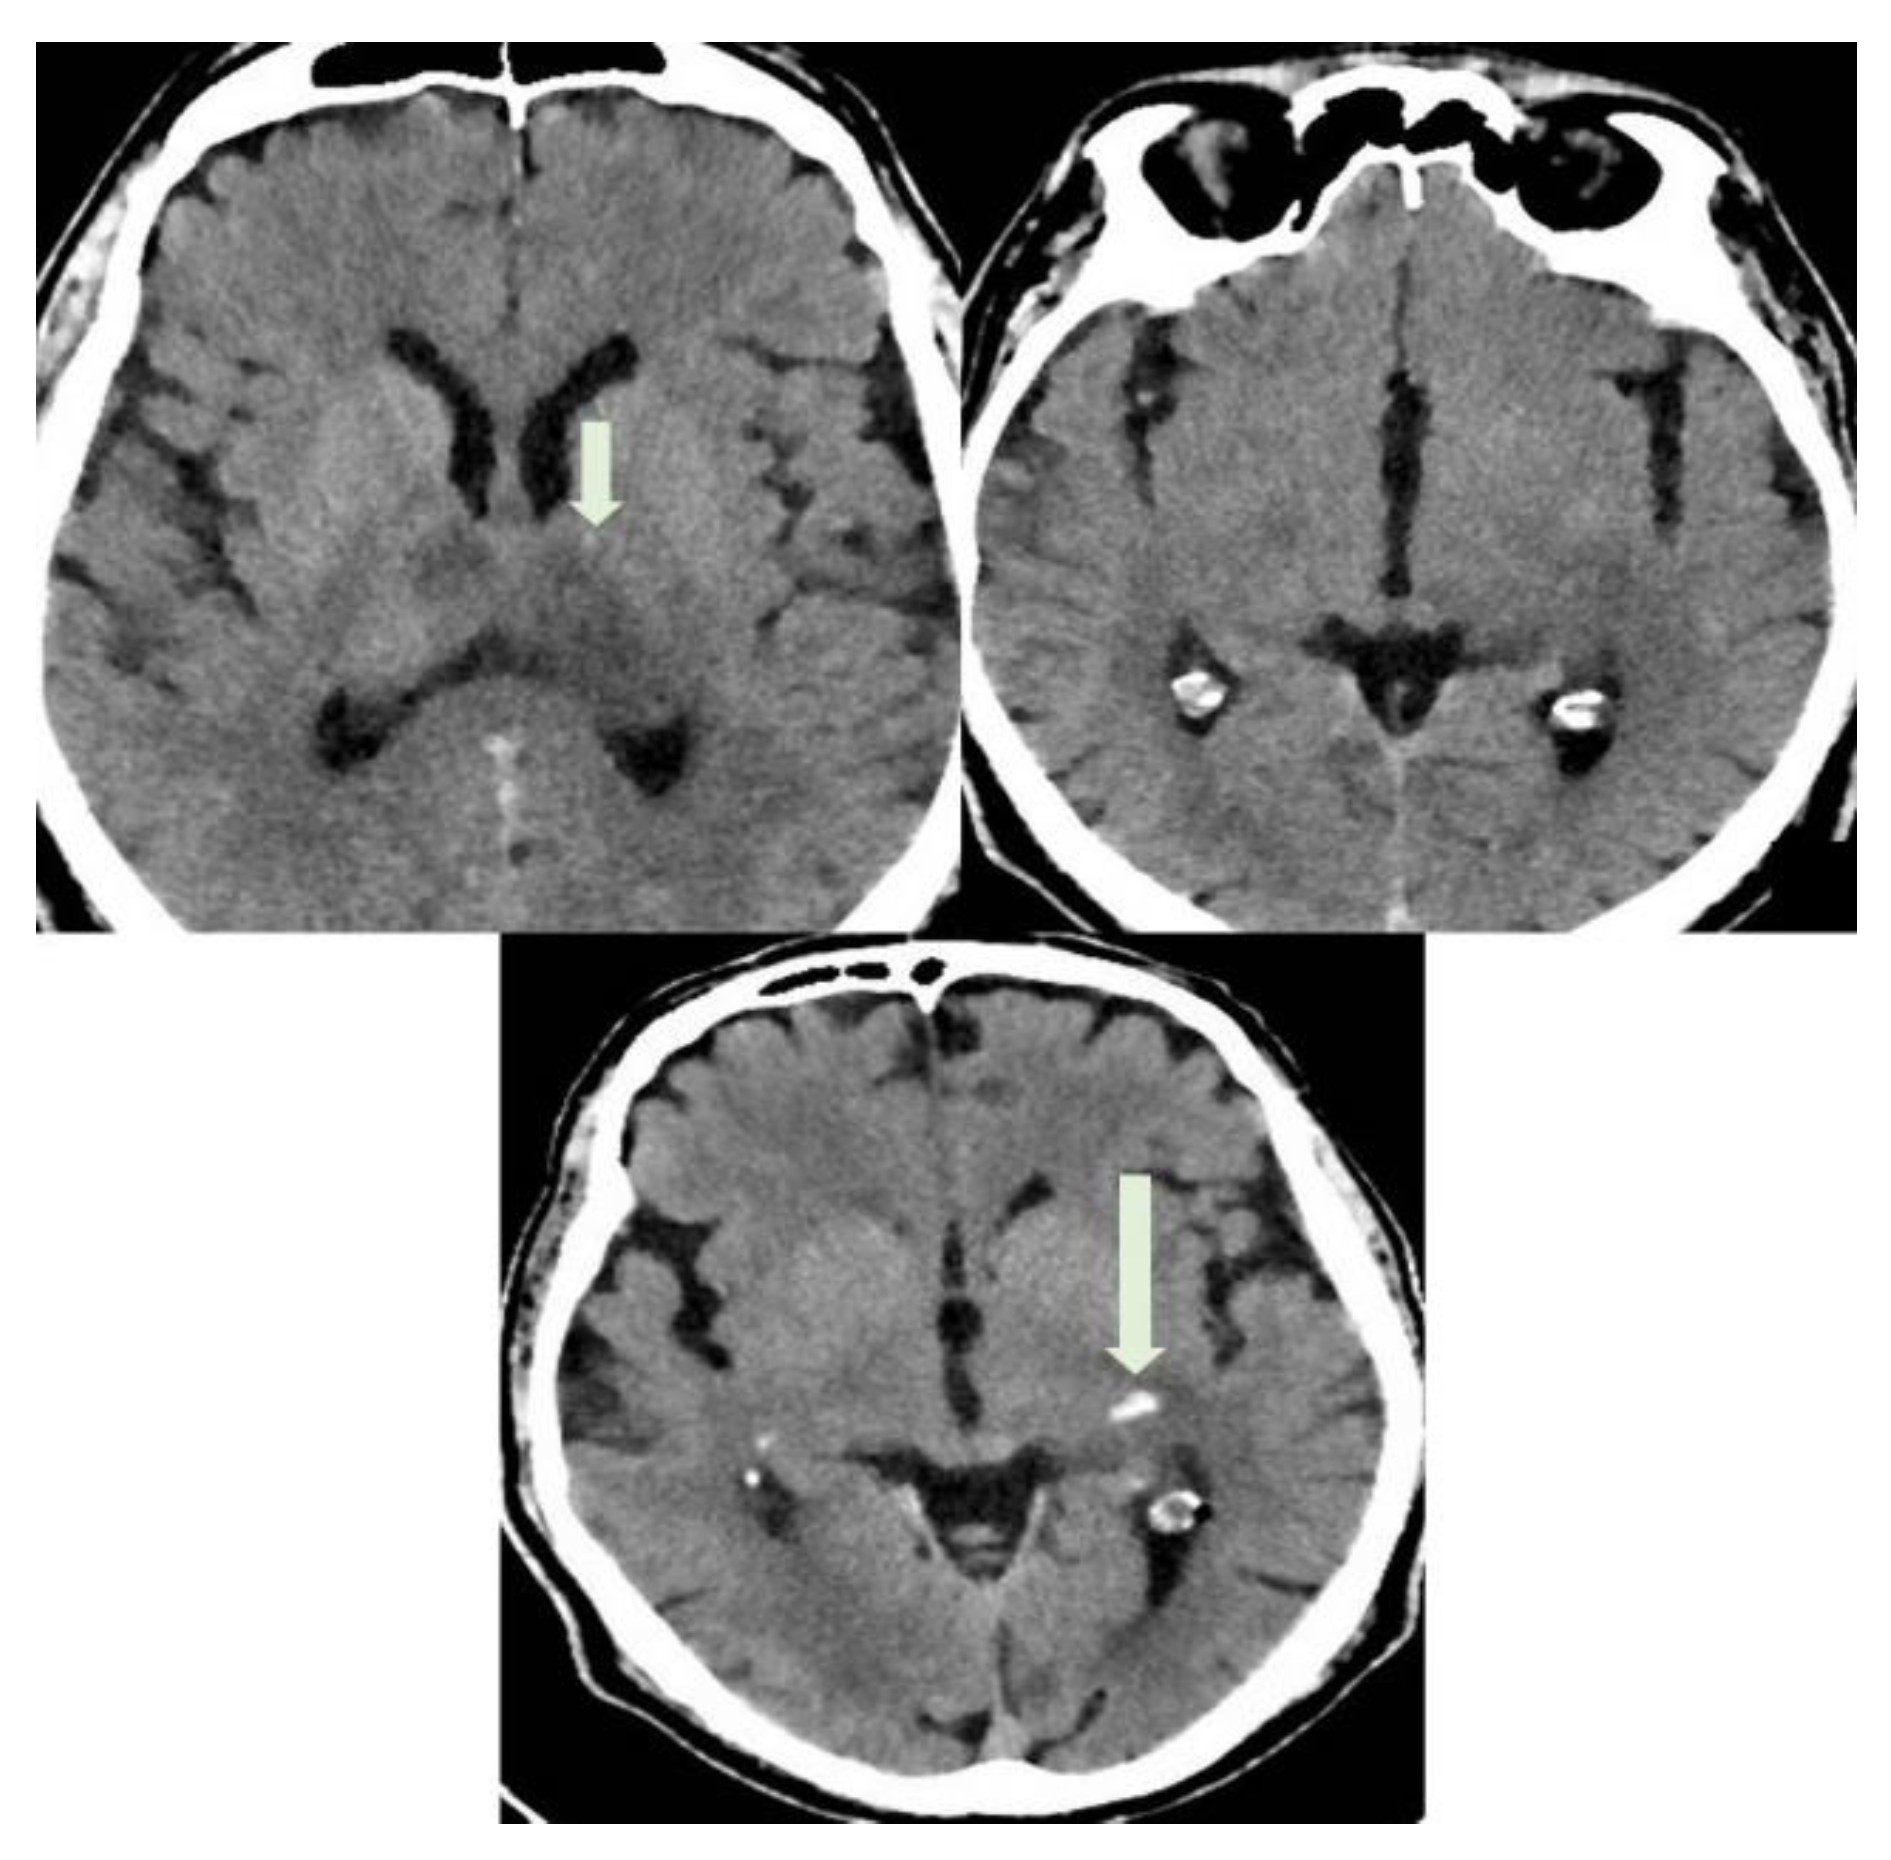

Brain MRI performed on a Philips Ingenia 3T MR system (Philips Healthcare, Best, The Netherlands), without medium contrast: (A) hyperintensity areas in both thalami (Axial T2-weighted image), (B,C) ischemic phenomena in thalami, left hippocampal and parahippocampal regions and haemorrhagic lesion in left parahippocampal region, view as hyperintense areas (Axial FLAIR-weighted images), (D,E) heavy metal deposits in the aforementioned regions (SWI, Susceptibility-Weighted Images), (F) ischemic lesion in the central portion of splenium of the corpus callosum (Sagittal FLAIR-weighted image). MRI was the first exam performed on the patient, a 56-year-old man who was hospitalized in July 2021 for severe asthenia, headache and acute confusional state, which started about 15 days after the first dose of Pfizer vaccine. The MRI sequences aforementioned allowed us to diagnose a subacute ischemic stroke. Chest X-ray, electrocardiogram and routine blood tests gave a negative response, except for high glycemic values (82 mmol/mol) and low platelets values (88 × 10−9/L) compared to the usual, normal patient’s platelet count. Genetic screening for coagulation disorders was negative.